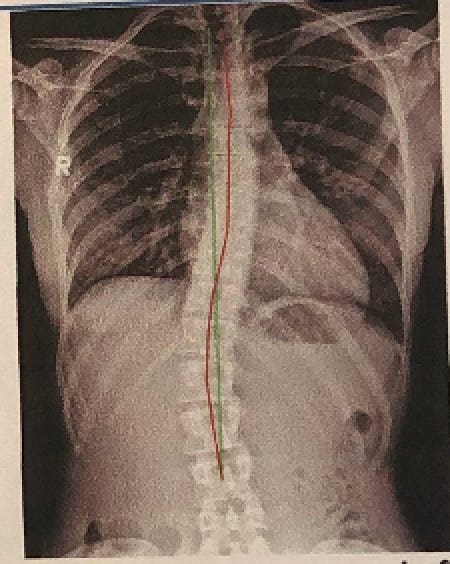

Without staying on top of my genetic imbalances, compensation can happen and happen quickly. Sometimes it’s a tight left hamstring, other times it’s been a tight left piriformis or a tight left calf. Lately it’s been a combination of all three, and it all stems from my scoliosis.

I was diagnosed with idiopathic scoliosis when I was 15 and the highest my curve ever measured was 23°—not terrible considering the degree of curvature that some of my family members have (thanks, Dutch genes! I got the scoliosis without the height.) It wasn’t enough to have me put in a brace nor be a candidate for surgery, and so I was sent to PT to complete endless clam shells.